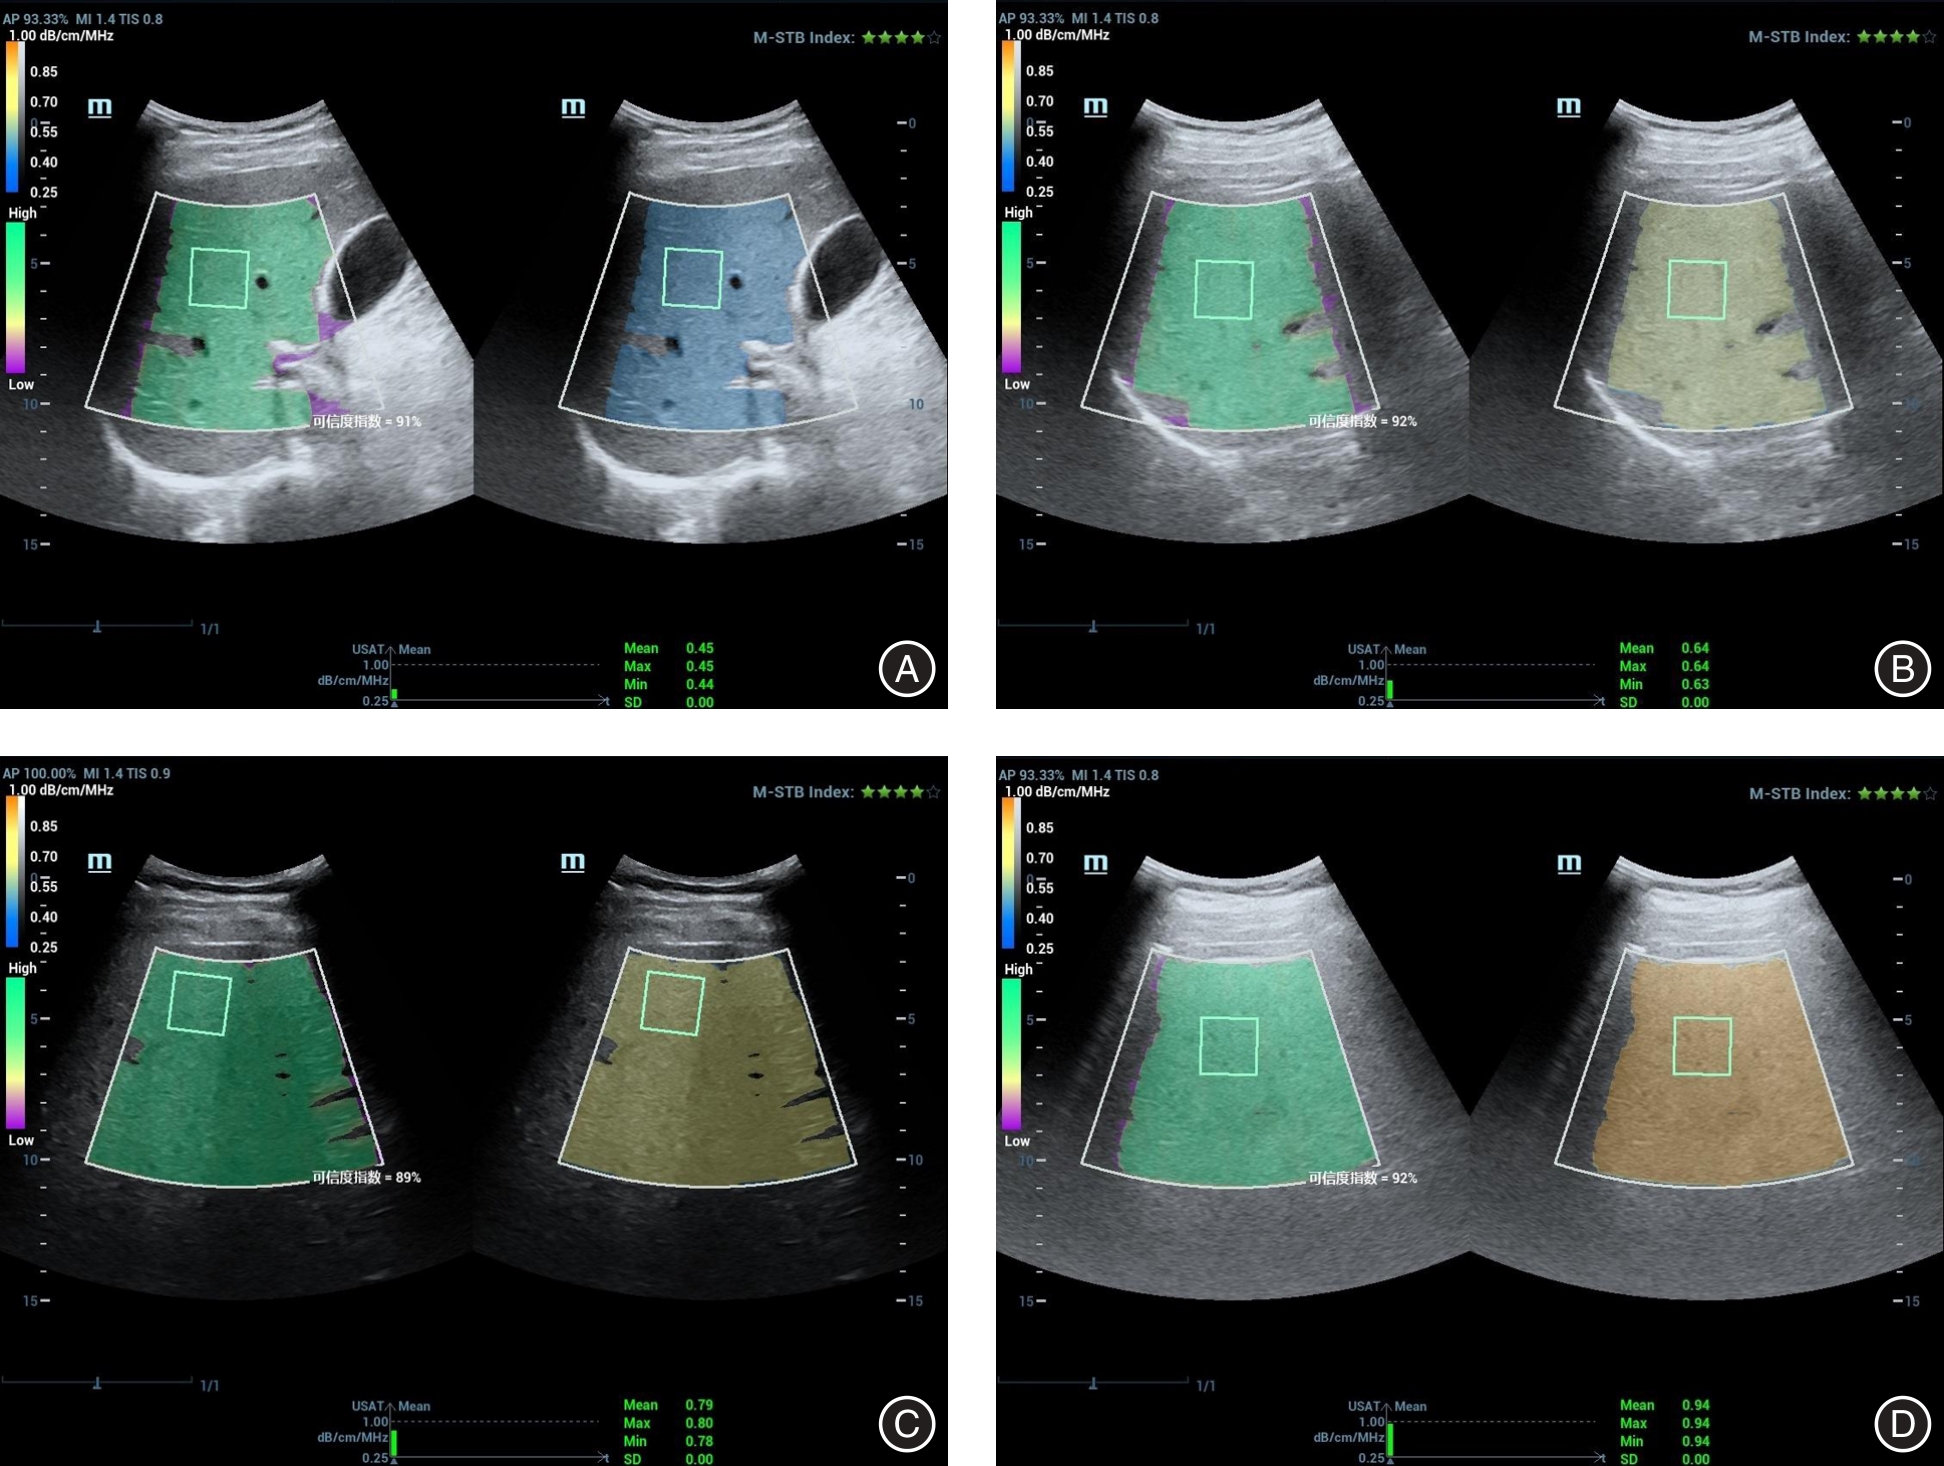

汪许红, 张盛敏, 杨敏, 等. 新型定量超声技术在非酒精性脂肪肝患者肝脏脂肪变性定量中的应用[J]. 中国超声医学杂志, 2021, 37(11): 1253-1257. doi:10.3969/j.issn.1002-0101. 2021.11.016 .